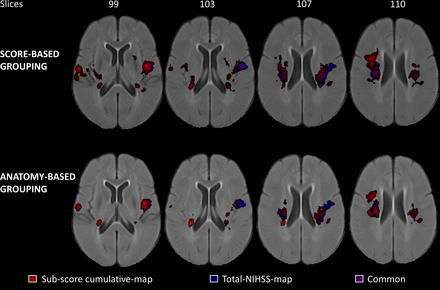

Lesion-symptom mapping with NIHSS sub-scores in ischemic stroke patients

Authors: Rajashekar, D., Wilms, M., MacDonald, M.E., Hill, M.D., Dukelow, S.P., and Forkert, N.D.

Journal: Stroke & Vascular Neurology: Volume 7, Issue 2

Background:

Lesion-symptom mapping (LSM) is a statistical technique to investigate the population-specific relationship between structural integrity and post-stroke clinical outcome. In clinical practice, patients are commonly evaluated using the National Institutes of Health Stroke Scale (NIHSS), an 11-domain clinical score to quantitate neurological deficits due to stroke. So far, LSM studies have mostly used the total NIHSS score for analysis, which might not uncover subtle structure–function relationships associated with the specific sub-domains of the NIHSS evaluation. Thus, the aim of this work was to investigate the feasibility to perform LSM analyses with sub-score information to reveal category-specific structure–function relationships that a total score may not reveal.

Methods:

Employing a multivariate technique, LSM analyses were conducted using a sample of 180 patients with NIHSS assessment at 48-hour post-stroke from the ESCAPE trial. The NIHSS domains were grouped into six categories using two schemes. LSM was conducted for each category of the two groupings and the total NIHSS score.

Results:

Sub-score LSMs not only identify most of the brain regions that are identified as critical by the total NIHSS score but also reveal additional brain regions critical to each function category of the NIHSS assessment without requiring extensive, specialised assessments.

Conclusion:

These findings show that widely available sub-scores of clinical outcome assessments can be used to investigate more specific structure–function relationships, which may improve predictive modelling of stroke outcomes in the context of modern clinical stroke assessments and neuroimaging.